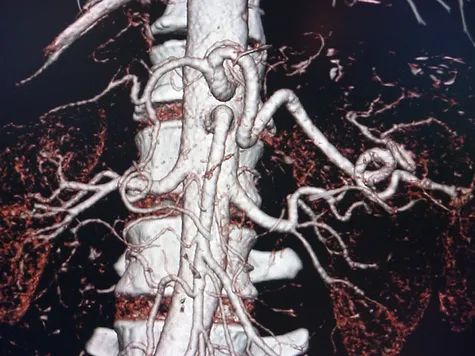

A hormone-secreting tumour that can occur in the adrenal glands. Phaeochromocytomas usually develop in the small glands on top of the kidneys (adrenal glands). They most commonly affect people between the ages of 20 and 50, but can occur at any age. Because of hormones secreted, symptoms include high blood pressure, sweating, rapid heartbeat and headache. Surgery to remove the tumour is usually required.